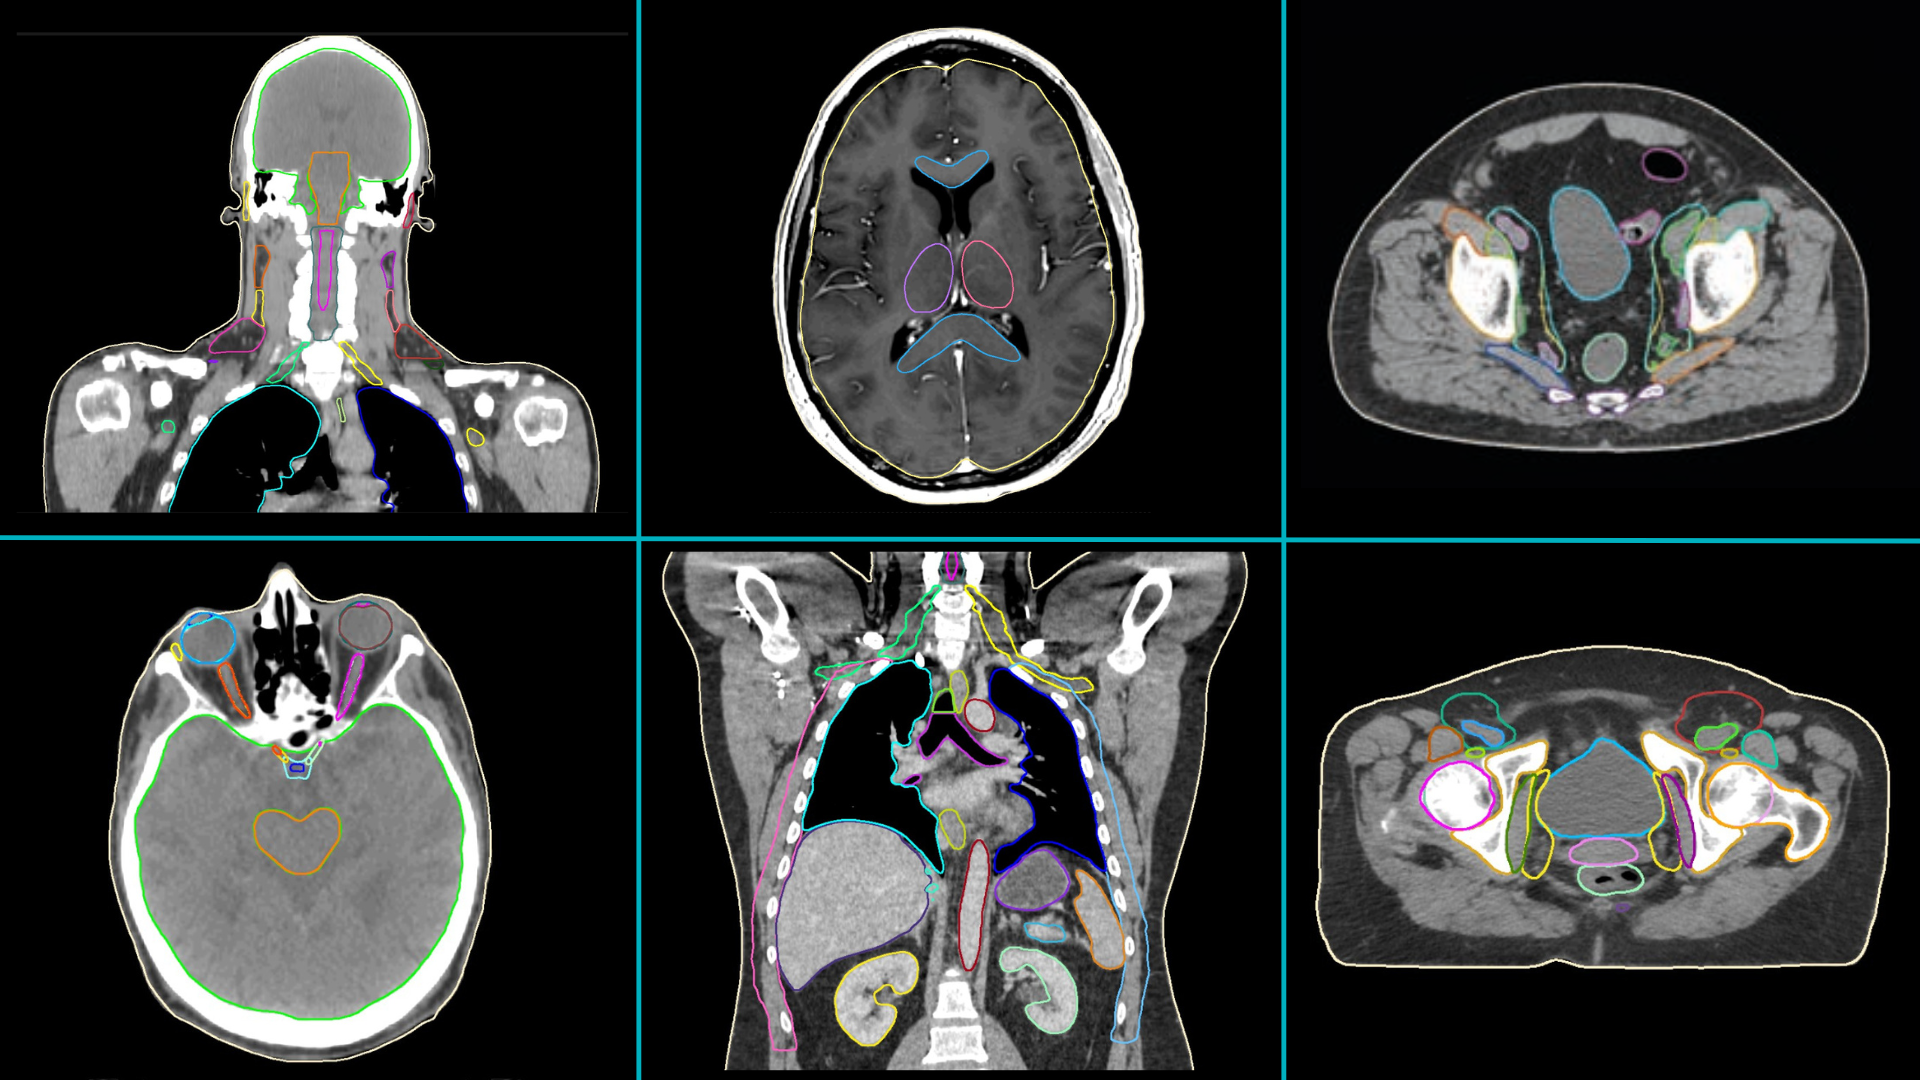

- Professionals working in 40 clinics from 31 countries assessed MVision AI’s Contour+ solution (Figure 1).

- Anatomical sites for which MVision AI models have been used for automatic contouring in the research projects (and the number of studies including them) are: male pelvis (9), breast (4), head and neck (4), thorax (3), female pelvis (3), brain (2), abdomen (2), heart (2), jaws (1) (Figure 3).